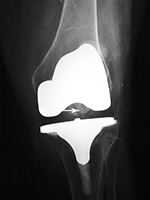

| Posterior cruciate retaining total knee prosthesis with cementless femoral and cemented tibial component and patellar resurfacing |

Stryker Triathlon PSC total knee arthroplasty

| There is a postoperative drain and skin staples. From Taljanovic, 2005 |

There is also a surgical drain and skin staples in place. 65 year-old woman. |